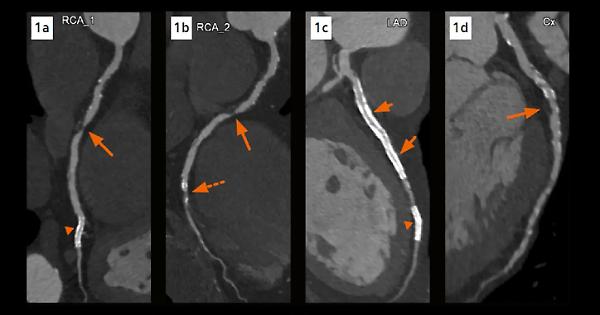

Al Congresso Europeo di Cardiologia di Madrid è stato presentato lo studio Pulse, un’analisi multicentrica che ha valutato l’efficacia della Tac coronarica di controllo nei pazienti sottoposti a stent nel tronco comune coronarico. I risultati, pubblicati sul Journal of the American College of Cardiology (JACC), mostrano che la Tac di follow-up non modifica i tassi di mortalità, ma riduce in modo significativo il rischio di infarto miocardico nei 18 mesi successivi rispetto al solo monitoraggio clinico dei sintomi.

Lo studio ha coinvolto 600 pazienti trattati con angioplastica e stent nel tronco comune, una delle aree coronariche più critiche. I partecipanti sono stati suddivisi in due gruppi: uno seguito con il tradizionale controllo clinico basato sui sintomi, l’altro con Tac coronarica di routine. Dal confronto è emerso che, pur senza incidere sulla sopravvivenza, la Tac riduce gli eventi ischemici maggiori nel breve-medio periodo.